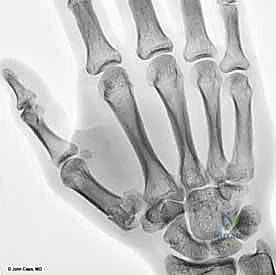

3. الكسور خارج المفصل (Extra-articular Fractures)

هي كسور تحدث في قاعدة عظم المشط الأول ولكنها لا تمتد إلى السطح المفصلي مع العظم المربعي.

* تكون إما كسوراً مستعرضة (Transverse) أو مائلة (Oblique).

* نظراً لأنها لا تؤثر على الغضروف المفصلي، فإن خطر الإصابة بخشونة المفاصل المستقبلية يكون أقل بكثير، وغالباً ما تستجيب بشكل ممتاز للعلاج التحفظي (التجصيص) إذا لم يكن هناك انحراف زاوي كبير (Angulation).